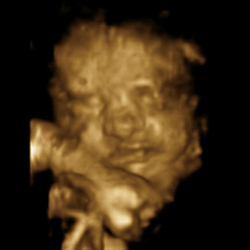

Been waiting ages to go get this done and it turned out to be worth the money and trip to Dublin from Leitrim! First proper look at the baby complete with smiles, waves & yawns in 2D, 3D and 4D!

Here’s some of the better poses (the first one is probably our favorite with the baby’s arms under it’s head!):

Those are really bringing the images to a new level.

More than a grainy ultrasound, you can see what the wee one actually looks like.

They still kind of freak me out a bit though…